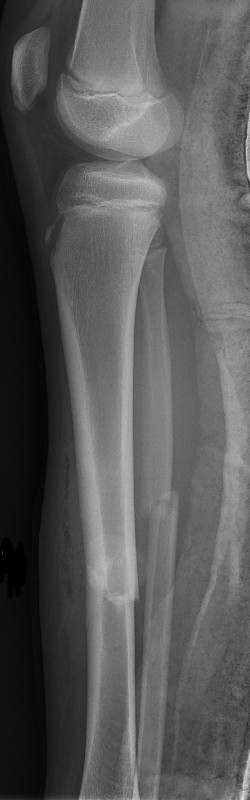

Tibiafraktur hos 7-åring, behandlades med gipsstövel